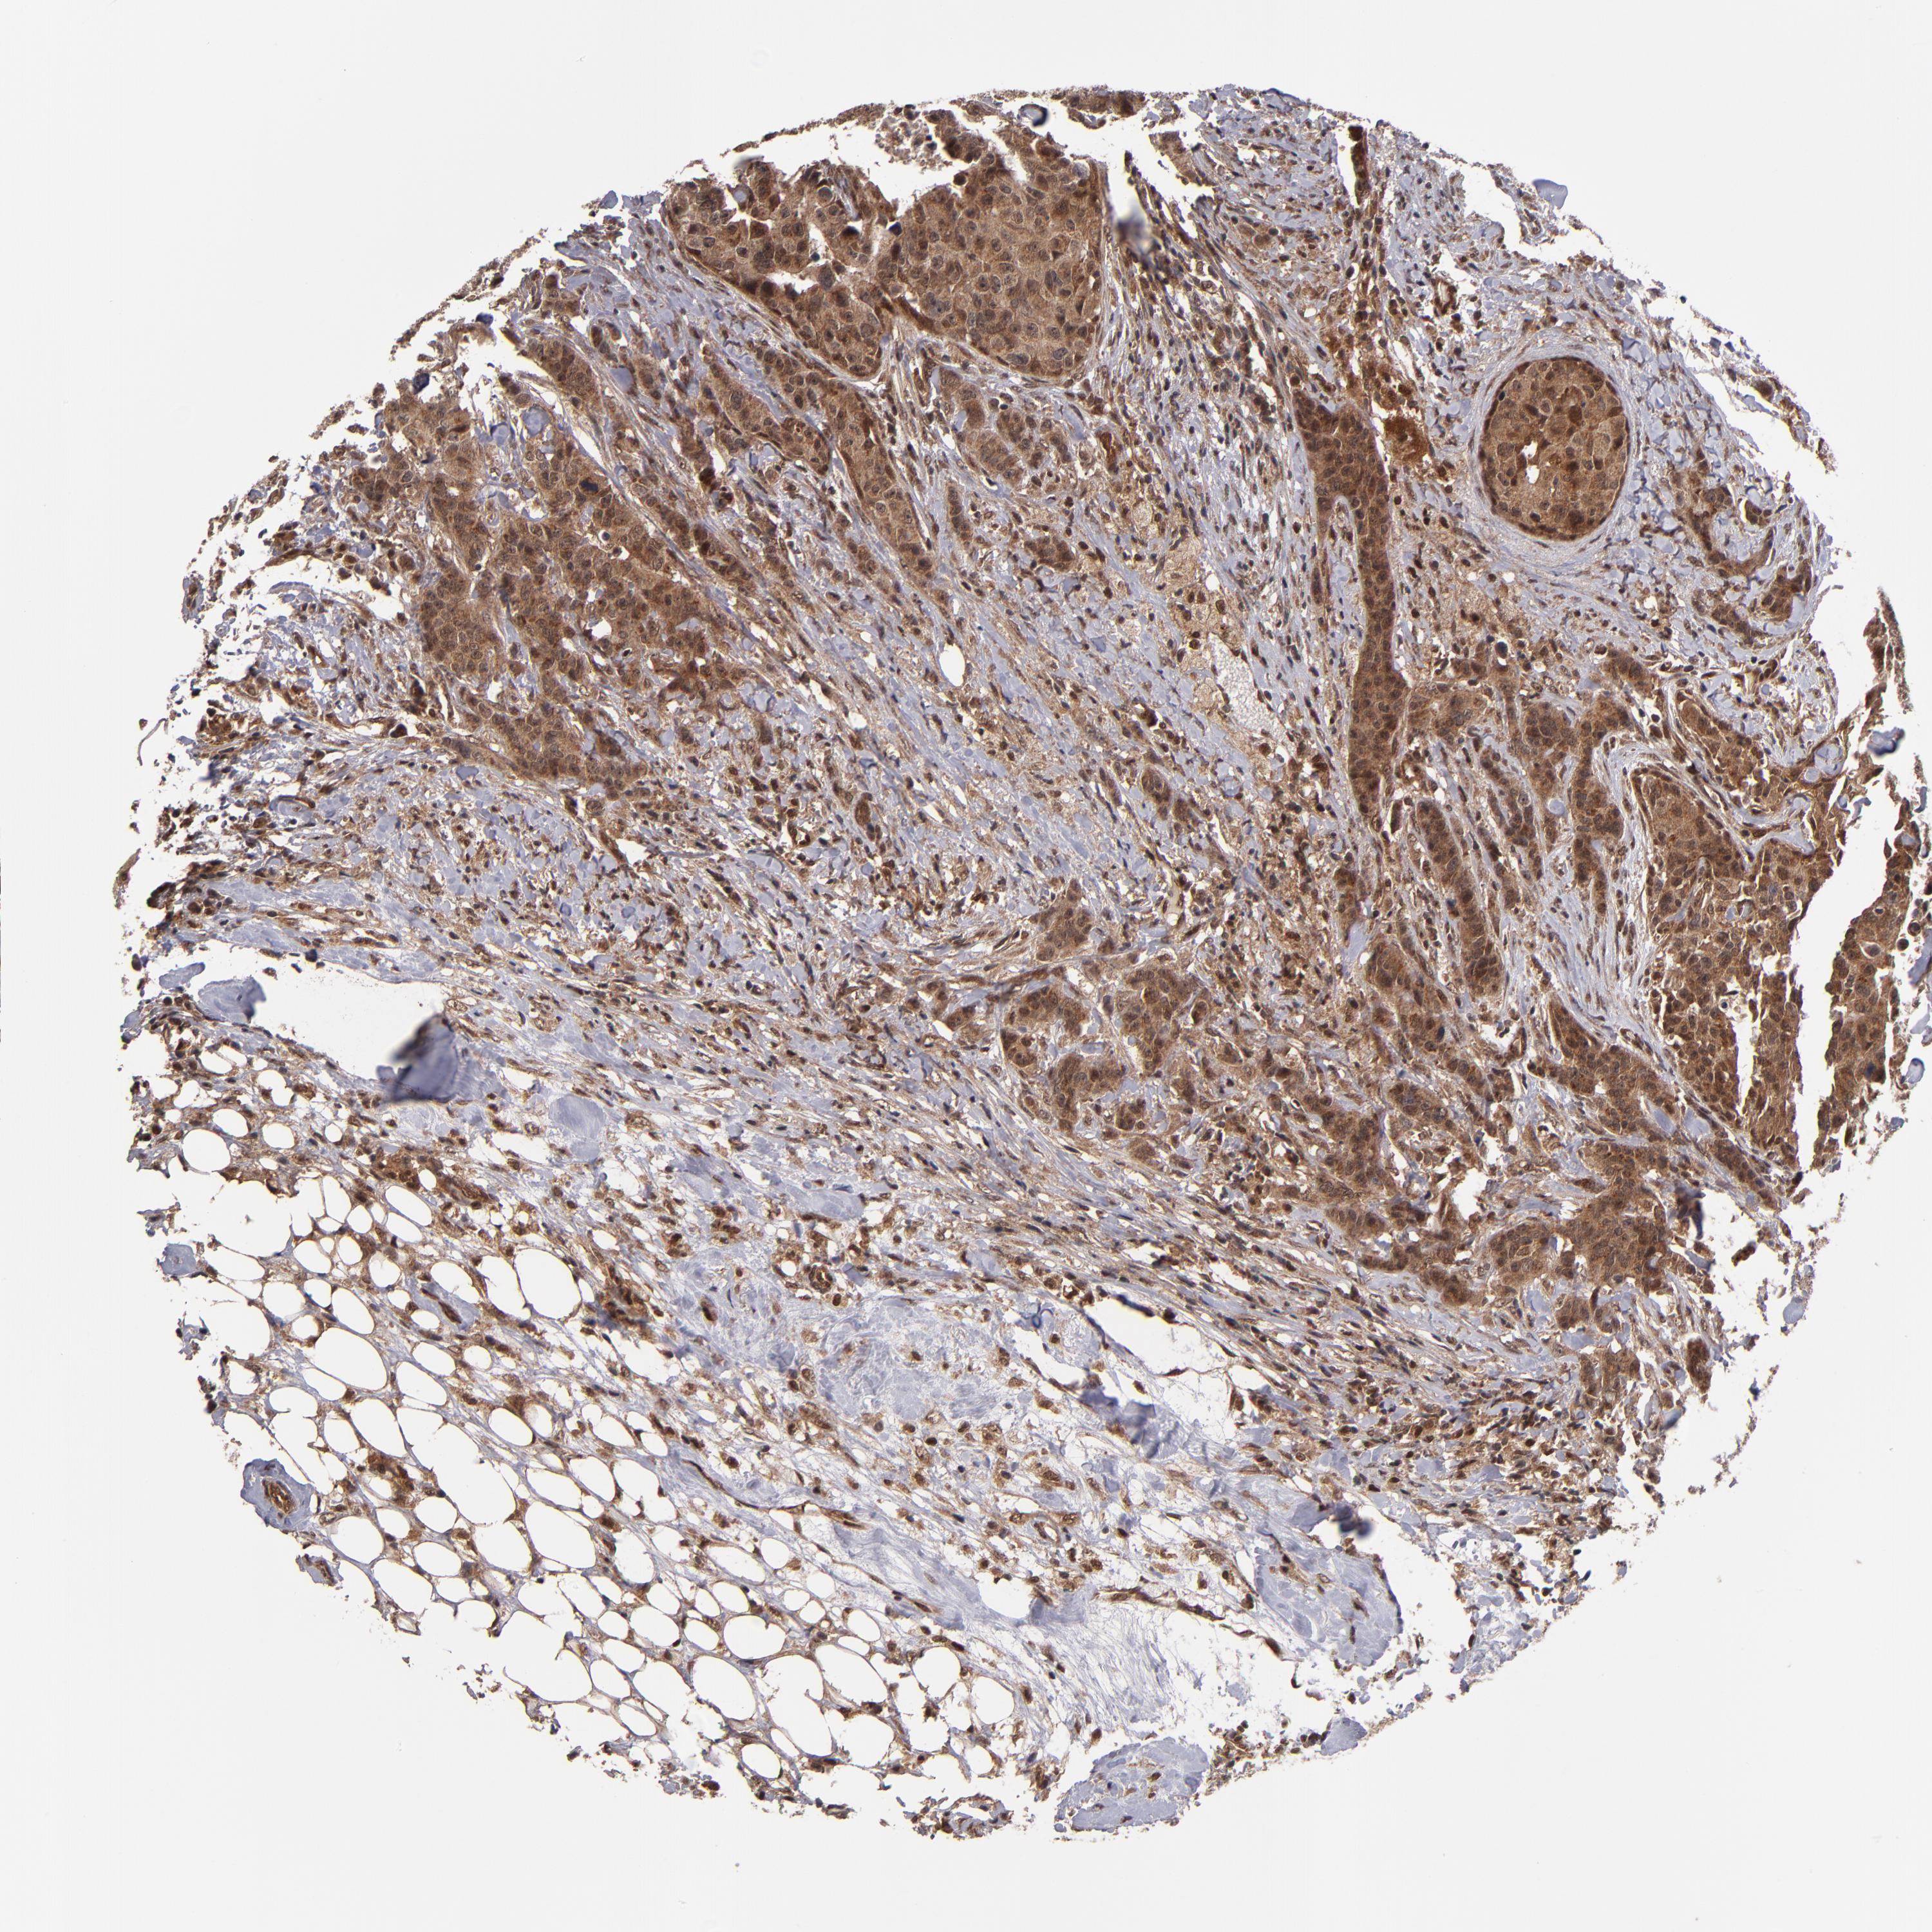

BRCA TCGA BRCA VALIDATION PROTEIN EXPRESSION

ANTIBODIES

AND

VALIDATION